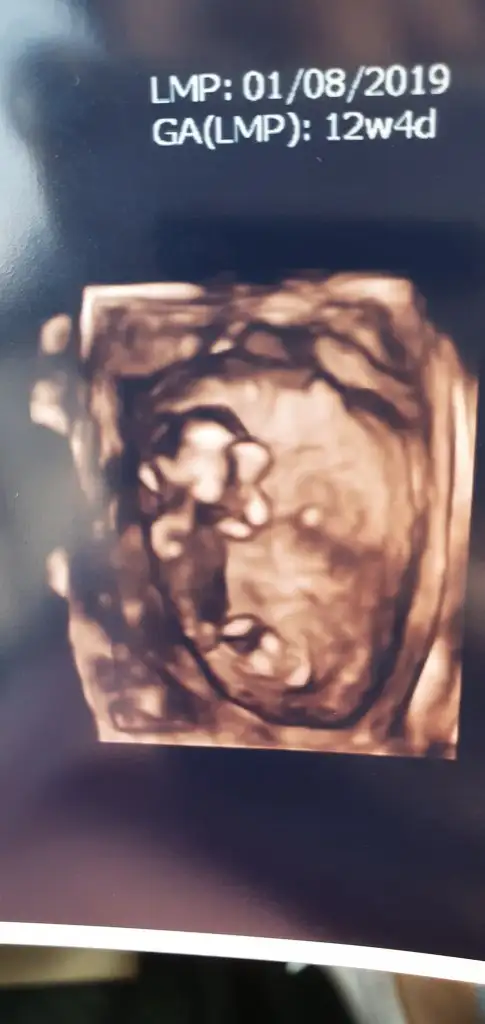

Kız gibi gibi diyorum başka usg varmıMerhaba benim bebeğim 12+3 sizce cinsiyet tahmininiz nedir nuba göre..? Şimdi ekliyorm usg Eki Görüntüle 2549218

Burda nub görünmüyor net degil renksiz usg paylaşırmısınızEki Görüntüle 2549000 sizce nedir

Kız gibi gibi diyorum başka usg varmı

Kız gibi bu usgler kaç haftaCevabınızı bekliyorum ve çok merak ediyorum.

12+3 haftalıkKız gibi bu usgler kaç hafta